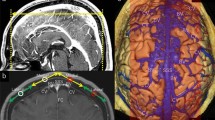

Diagnosis was carried out by members of this study group, a panel consisting of nine neurosurgeons and three neuroradiologists, all but one (K.T.) certified as neuro-interventionalists by the JSNET. All collected angiographic data were reviewed using Horos v.3.3.6, a free, open-source medical image viewer. The 3D data of posterior fossa veins were evaluated mainly using slab MIP images from CE-CBCT or venous phase 3D-RA. Because CE-CBCT with long acquisition mode included data on arteries and veins, we distinguished arteries and veins using CE-CBCT and arterial phase 3D-RA data (Fig. 1). We defined the BVs as including the radiculomedullary veins, which run along the cranial and spinal nerve roots. We analyzed the course, outlet, and number of BVs around the FM in each patient. We also examined the detection rate and mean diameter of each BV.

Differentiation between arteries and veins in contrast-enhanced cone-beam CT (CE-CBCT). The axial view of the slab MIP images of CE-CBCT (a) and arterial phase three-dimensional rotational angiography (b). CE-CBCT with long acquisition mode includes data on arteries and veins. We can only observe arteries (arrow) in arterial phase three-dimensional rotational angiography (b). Consequently, we can confirm that the other vessels are veins (white and black arrowheads) or sinuses (double arrows) in CE-CBCT (a). Star shows the left vertebral artery

Schematic illustration (a) and its partly expanded illustration (b) of bridging veins (BVs) and surrounding vessels around the foramen magnum: 1 indicates the anterior condylar vein (ACV) BV; 2, jugular foramen (JF) BV; 3, marginal sinus (MS) BV; 4, suboccipital cavernous sinus (SCS) BV; 5, cerebellomedullary cistern (CMC) BV; 6, cross-section of the medulla oblongata; 7, basilar artery; 8, vertebral artery (VA); 9, ACV in the hypoglossal canal; 10, jugular bulb or sigmoid sinus; 11, MS; 12, SCS around the extracranial VA; 13, occipital sinus